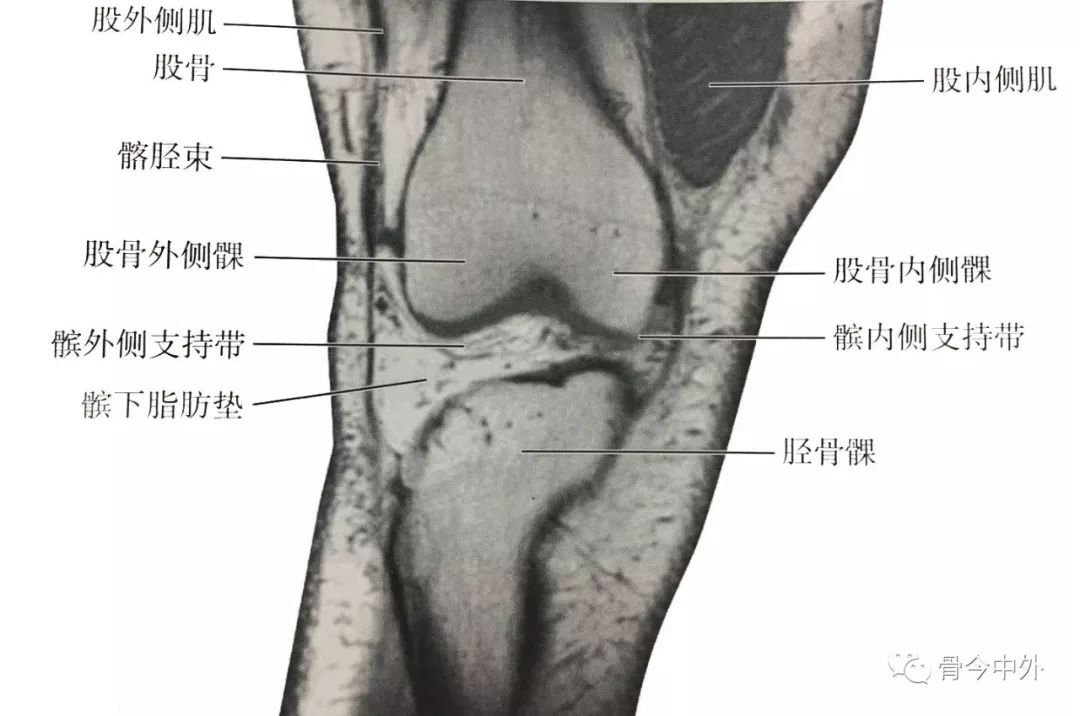

(1)膝前部冠状断层:该层面解剖关系结构如图

膝前部冠状断层